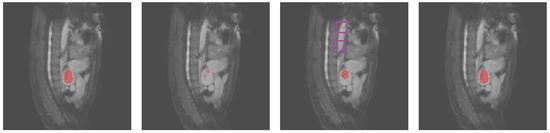

3.2. Results Obtained on the Heart MRI Dataset